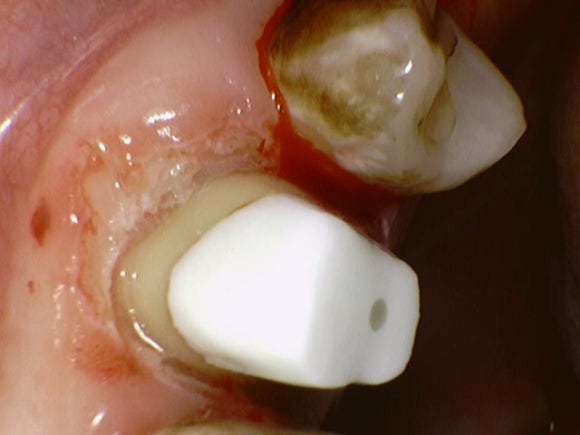

충치를 일단 제거해봤습니다.

뿌리는 멀쩡해보입니다.

이 뿌리를 살려서 써볼 수 있을까?

잠시 고민해봅니다.

그럴땐 치은절제술을 통해 뿌리의 일부를 노출시킵니다.

위 사진은 충치를 모두 제거하고 치은절제술로 뿌리를 노출시킨 사진입니다.